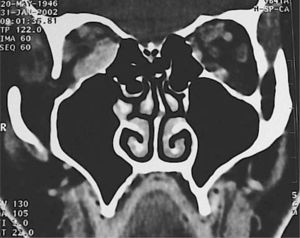

Esta técnica quirúrgica puede asociarse a la extirpación de otra pared orbitaria, el piso logrando un mayor volumen y por ende una disminución de la proptosis. (Figuras 3A y 3B).